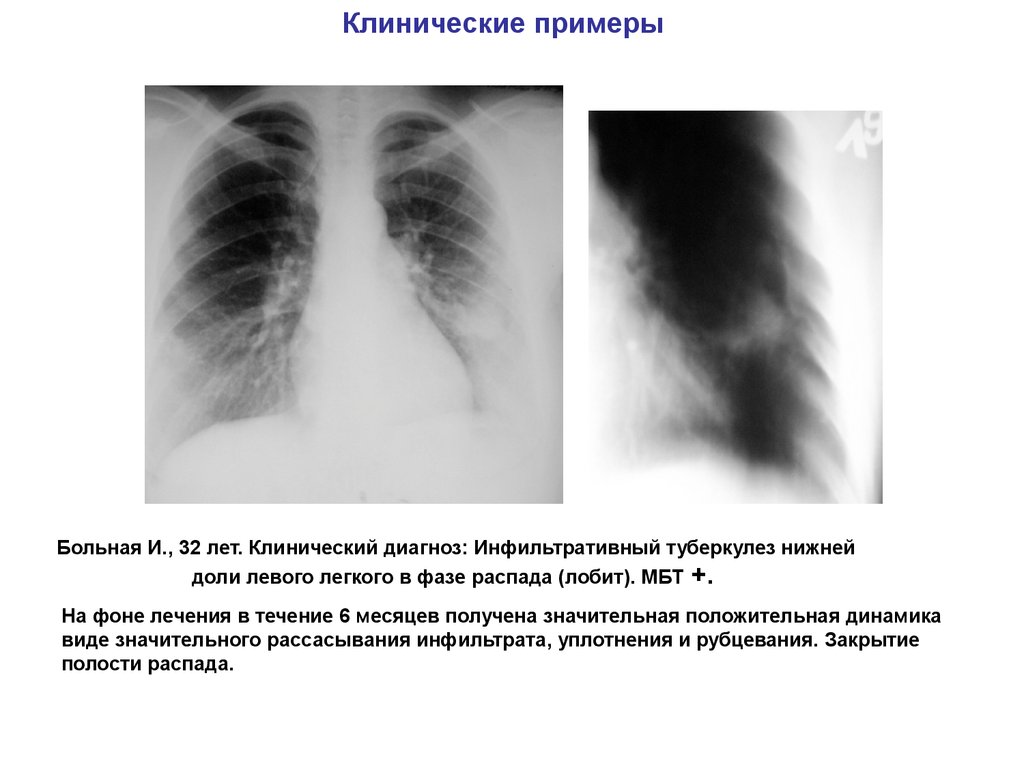

Очаговый и инфильтративный туберкулез презентация - 94 фото